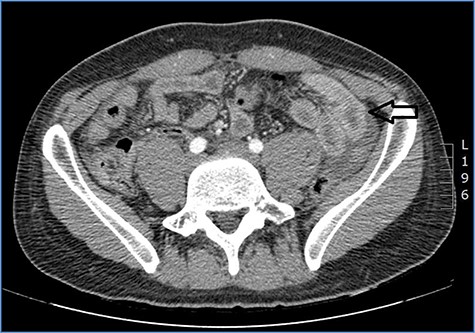

fluid collection in the peritoneal cavity. Subsequent CT confirmed the presence of diffuse fluid collection in the peritoneal cavity (Fig. 1) but no free air, with distention, bundling and thickening of some small bowel in the left quadrant (Fig. 2). The patient was therefore admitted for supporting therapy (intravenous fluids and antibiotics) with the suspicion of cocaine-induced small bowel ischemia. Twelve hours later, signs and symptoms of diffuse peritonitis developed: worsening diffuse abdominal pain with rebound guarding at examination, a significant increase in WBCs count (16.15 × 103/μl) and neutrophilia (88%), lengthening of coagulation times (INR: 1.68; aPTT: 33.0 s) and increase in fibrinogen (430 mg/dl) and D-Dimer (2275 ng/ml). Therefore, urgent surgical exploration of the abdomen through a three-port open laparoscopic approach was performed, confirming the presence of 1200 ml of exudative fluid and fibrin clots (Fig. 3). Several adhesions between greater omentum, abdominal wall and small bowel underwent blunt dissection. Thorough exploration of the small bowel revealed two ischemic segments located at about 50 and 100 cm from the Treitz ligament (Fig. 4). The large bowel appeared normal. The existence of non-visible gastro-duodenal perforations was ruled out with the administration of 500 ml of saline with 20 ml of methylene blue through the nasogastric tube. An iv bolus of sodium heparin, 10 000 IU, was then administered, performing a 30-min peritoneal lavage with 5 l of saline solution at 37°C. After reaspiration of peritoneal lavage, a new complete exploration of the small bowel was performed, showing complete revascularization of the two ischemic small bowel segments (Fig. 5). Two tubular drainage tubes were placed in the left and right colic gutters. Culture examination of peritoneal exudate was positive for multi-sensitive Escherichia coli and Enterococcus, thus confirming bacterial translocation peritonitis. Postoperative therapy included the administration of iv piperacillin–tazobactam and subcutaneous low molecular weight heparin. Postoperative recovery was smooth, with oral feeding on the second postoperative day (POD), drainage removal on POD 3, complete bowel function restored on POD 4 and home discharge on POD 5. At 15- and 30-day-follow-up, the patient showed full recovery, being now followed by a specialized support structure for his drug abuse.